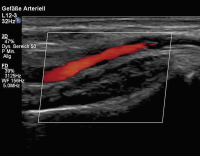

Duplexsonographie

Abbildung 3: Duplexsonographischer Befund mit regelrechtem, pulsatilem Fluss der Arteria radialis ohne Stenosierung oder Verschluss nach der Biopsie.

Keywords: Arteria radialisBefundDuplexsonographieKardiologiepulsatiler Fluss